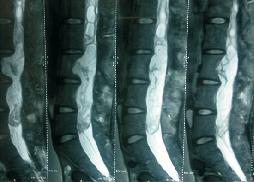

Percutaneous Spinal Fixation

Spondy-Lolisthesis